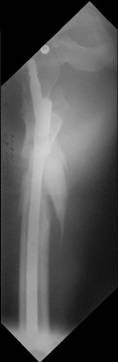

Re: Severely comminuted Trochenteric #

I would use a small wire distractor mentioned in the list some times. Proximal wire is in the iliac crest in AP direction. The leg is adducted. I attached some images. At the AP view under image intensifier you can see adduction but even slight valgus reduction.